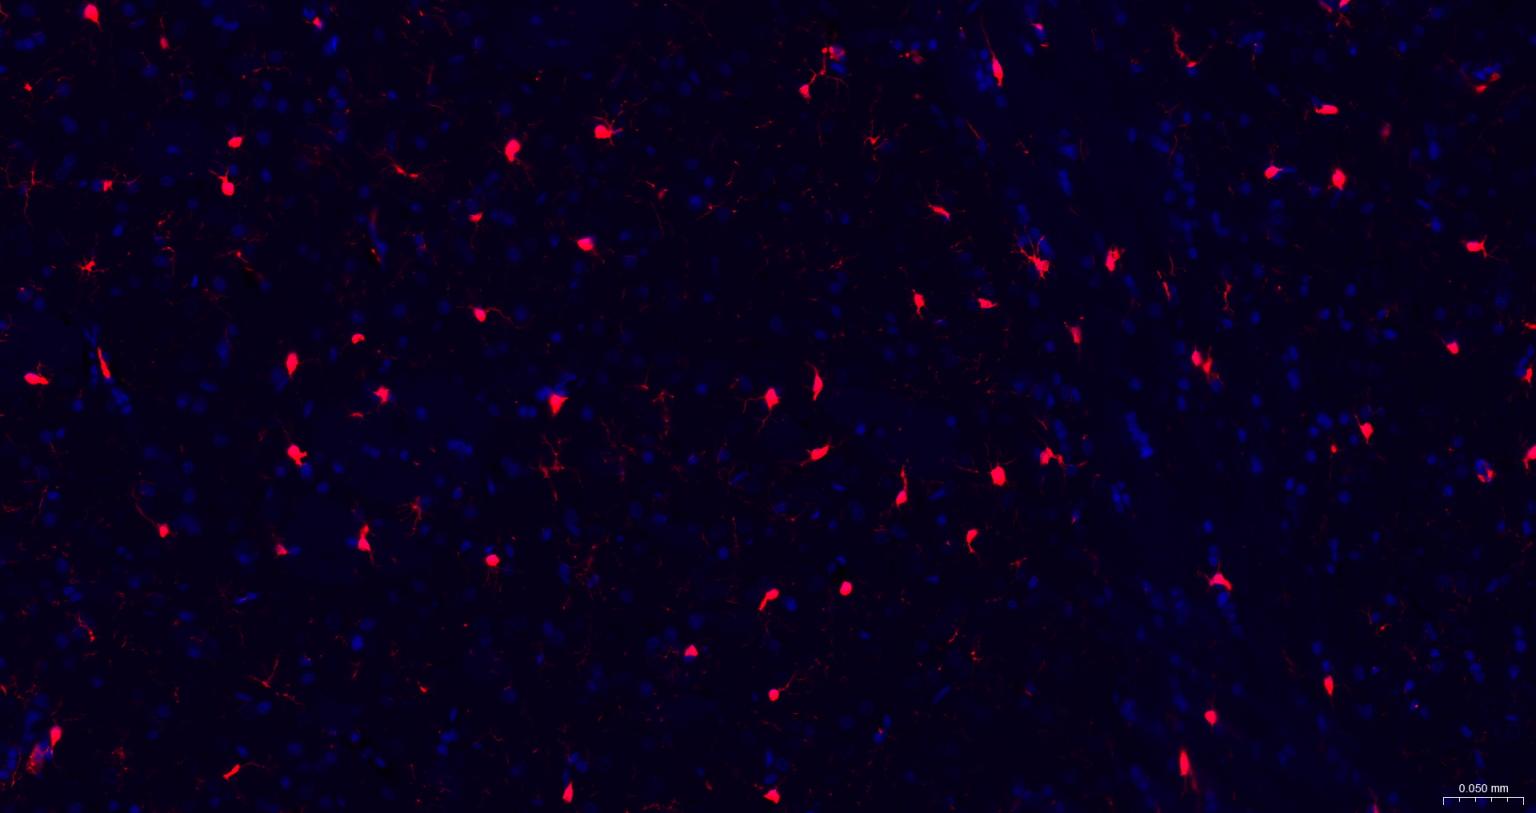

Paraformaldehyde-fixed, paraffin embedded Mouse Cerebrum; Antigen retrieval by boiling in sodium citrate buffer (pH6.0) for 15 min; The section was incubated with AIF1 / Iba1 Polyclonal Antibody, Unconjugated (bs-1363R) at 1:200 overnight at 4°C. Followed by conjugated Goat Anti-Rabbit IgG antibody (Red, bs-0295G-BF594), DAPI (blue, C02-04002) was used to stain the cell nuclei.